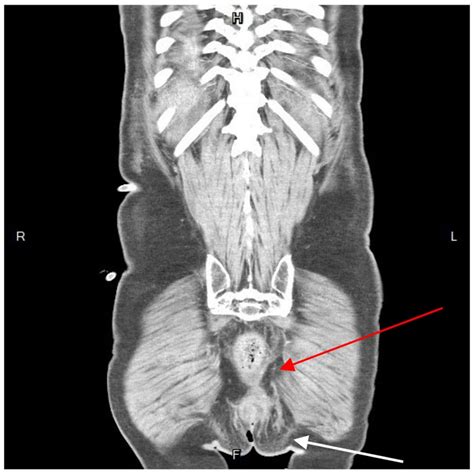

Diagnosing a perianal abscess typically involves a physical examination by a healthcare provider. The doctor will examine the affected area and may ask about symptoms and medical history. In some cases, additional tests may be necessary to confirm the diagnosis or rule out other conditions. These tests may include:

• Imaging Tests: Such as an ultrasound or CT scan to visualize the abscess and surrounding tissues.

Perianal Abscesses Pictures

Visual aids can be incredibly helpful in understanding medical conditions. While it’s important to note that viewing perianal abscesses pictures can be graphic and may not be suitable for all audiences, they can provide a clear understanding of what these abscesses look like. These images often show the redness, swelling, and drainage associated with the condition. If you are considering viewing such images, it is advisable to do so under the guidance of a healthcare professional.